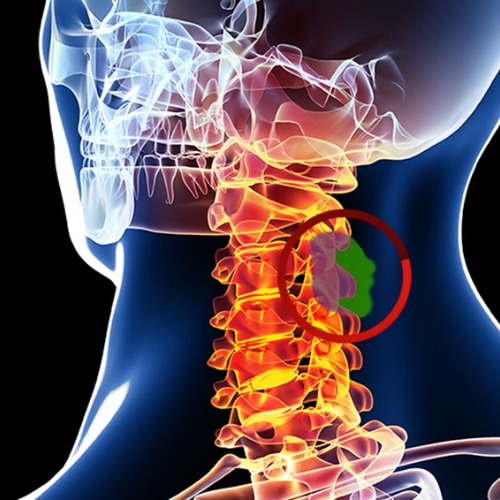

Spine Surgery

Spine surgery corrects structural or nerve-related spinal problems. Using minimally invasive methods, it relieves pain, restores stability, and enhances mobility for better spinal health.